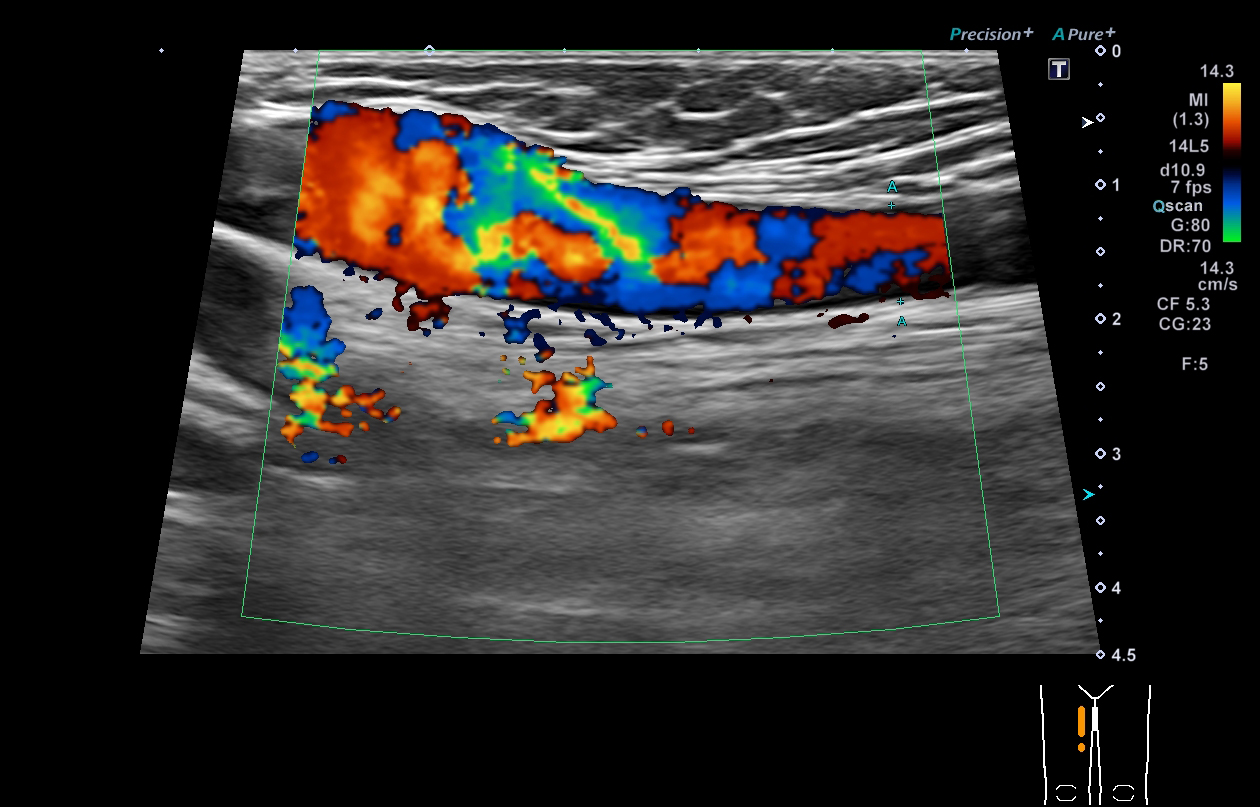

超音波(エコー) 診断画像

- 内頸動脈狭窄

- 静脈瘤